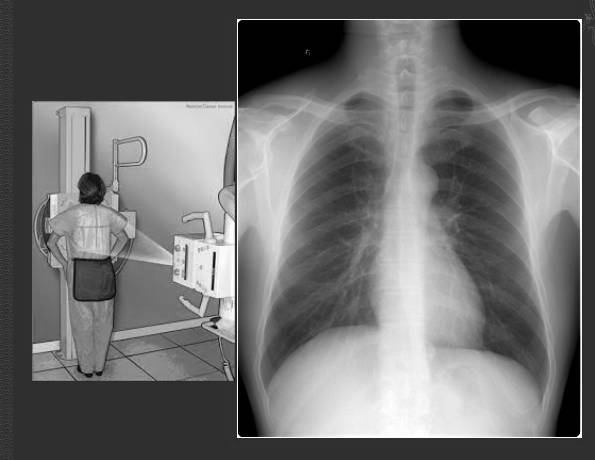

6步法从胸片进行胸部评估

如何拍胸片照片

胸片怎么照

胸片怎么看